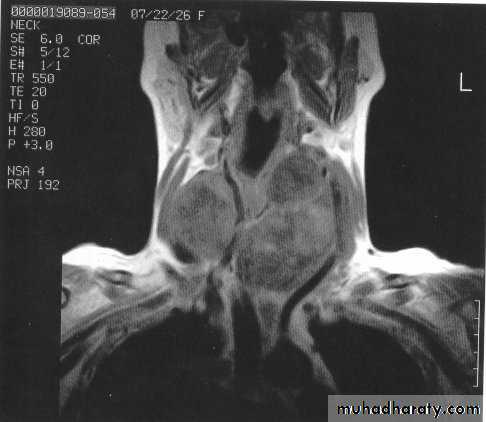

D-Imaging study1-plan X ray of the neck: to evaluate the trachea, retrosternal extension and cervical spine . 2-Ultrasound: distinguishing solid from cystic masses, information about size and multicentricity, assess cervical lymph nodes and guides for FNAC.

3-CT scan and MRI: assessment of known malignancy, extent of retrosternal and occasionally recurrent

Goitres.